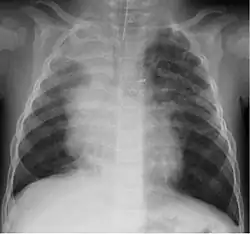

Um estudo na Jordânia constatou que 9% das 220 crianças hospitalizadas com infecção no trato respiratório inferior haviam sido infectadas pelo bocavírus.[23] Entre elas, a idade mediana era de 4 meses. Tosse (100%), sibilo (82.7%) e febre (68.2%) eram os achados clínicos mais comuns, com broncopneumonia (35%) e bronquiolite (30%) sendo os diagnósticos finais mais frequentes.

Embora a maioria dos casos seja leve, já foram relatados casos de doenças respiratórias graves causadas pelo bocavírus humano.[24]